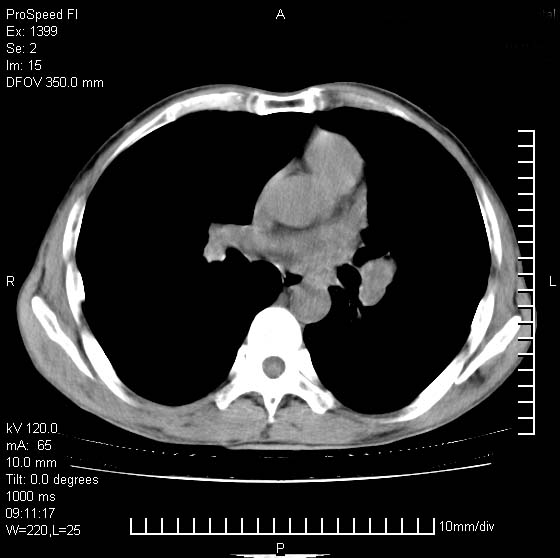

以下是引用卜一在2007-1-19 9:55:00的发言:[br]左肺沿胸膜下巨大肿块影,边缘呈分叶征,纵隔内见肿大淋巴结,右肺内另见一不规则结节影 .考虑:左肺周围性肺癌伴纵隔 右肺内转移.

以下是引用rgsyyf在2007-1-19 11:05:00的发言:[br]左肺上叶见形态不规则巨大软组织肿块影,边缘呈分叶征,纵隔内隆突下见肿大淋巴结,右肺内另见一不规则结节影 .考虑:左肺周围性肺癌伴纵隔即右肺内转移.